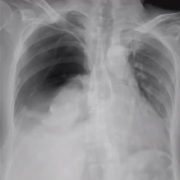

发生率 27-54%,3-15%需要穿刺引流 气胸的危险因素 COPD 肺气肿 同侧外科手术的历史 年龄 技术因素 胸膜下病变Subpleural lesions 胸膜穿刺的次数N of pleural punctures Wider insertion of the needle 穿刺路径深Long needle path 针穿过胸膜的时间 time o...